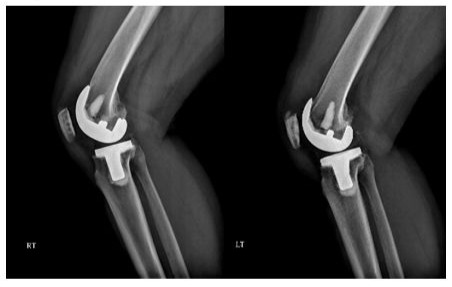

Radiographs of the knees of a 65-year-old woman who had osteoarthritis in both knees (Figure 3).

Figure 3A: Standing anteroposterior radiograph of both knees taken 4 years after surgery, showing that the Freedom knee prostheses are embedded solidly in a satisfactory position. There are no radiolucent lines and there is no osteolysis around the components in either knee.

Figure 3B: Lateral radiographs showing that the Freedom knee prostheses are fixed satisfactorily. There are no radiolucent lines and there is no osteolysis around the components in either knee.

The radiographic results were similar in the NexGen LS-Flex and Freedom TKA groups with regard to the alignment of the knee and the position of the femoral and tibial components in the coronal and sagittal planes. If one assumes a tolerance level of 3°, then the prevalence of outliers ranged from 2 to 4% for all parameters in the NexGen LPS-Flex TKA group and from 1 to 3% in the Freedom TKA group. These differences between the groups were not significant (P > 0.05; Table 4). No knee in either group had osteolysis around the components (Figures 2 and 3).